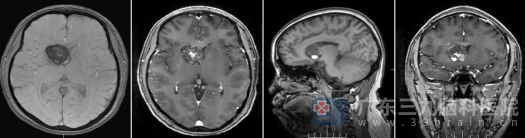

入院后,神经外十科团队为凌某完善了高磁场、高分辨率头颅MR及SWI序列检查。结果清晰显示:右侧基底节区、放射冠多发病变,较大者约25mm×22mm,明确诊断为“海绵状血管畸形”,并合并发育性静脉异常。

面对挑战,神经外十科团队组织了多次术前讨论,制定了精细化的手术入路与应急预案。在征得患者及家属充分知情同意后,在欧阳辉教授和林德留主任的带领下,在神经导航与高精度显微镜辅助下,右侧纵裂入路,手术历时5小时,于毫厘之间完整切除病灶,术中成功避开了周围重要的神经传导束与大脑前动脉。

术后凌某恢复顺利,复查头颅MR显示病灶全切,无残留。术后病理证实为“海绵状血管畸形,伴出血及胶质细胞反应性增生”。出院时,凌某神志清醒,语言流利,四肢活动自如,未出现任何新增神经功能缺损。